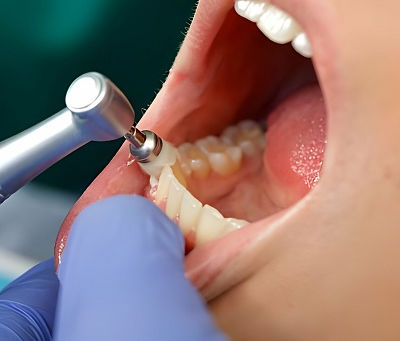

The Science Behind Teeth Cleaning and Oral Health

For anyone seeking a healthier, brighter smile, Teeth Cleaning Dubai offers more than just a cosmetic upgrade—it’s a vital step in...

Teeth Cleaning Tips for a Brighter Smile

A bright, healthy smile often starts with proper dental care and routine Teeth Cleaning in Dubai . While cosmetic treatments can enhance...